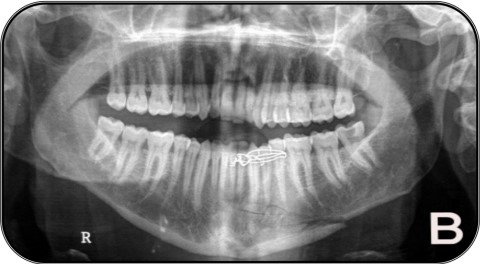

Extra-oral MultiDirectional Distractor: A Multi Uses Distractor1